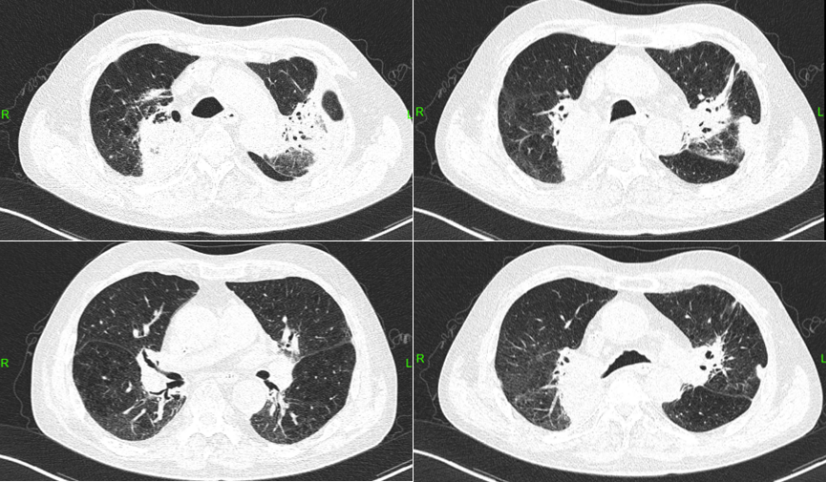

患者入院第1天(2023-08-03)胸部CT示:右上肺团片影较前明显增大,边缘不清,周围有实变,右上叶支气管管腔通畅远端见较多斑片渗出影双肺下叶间质改变(1)

1  患者入院前后胸部CT比较